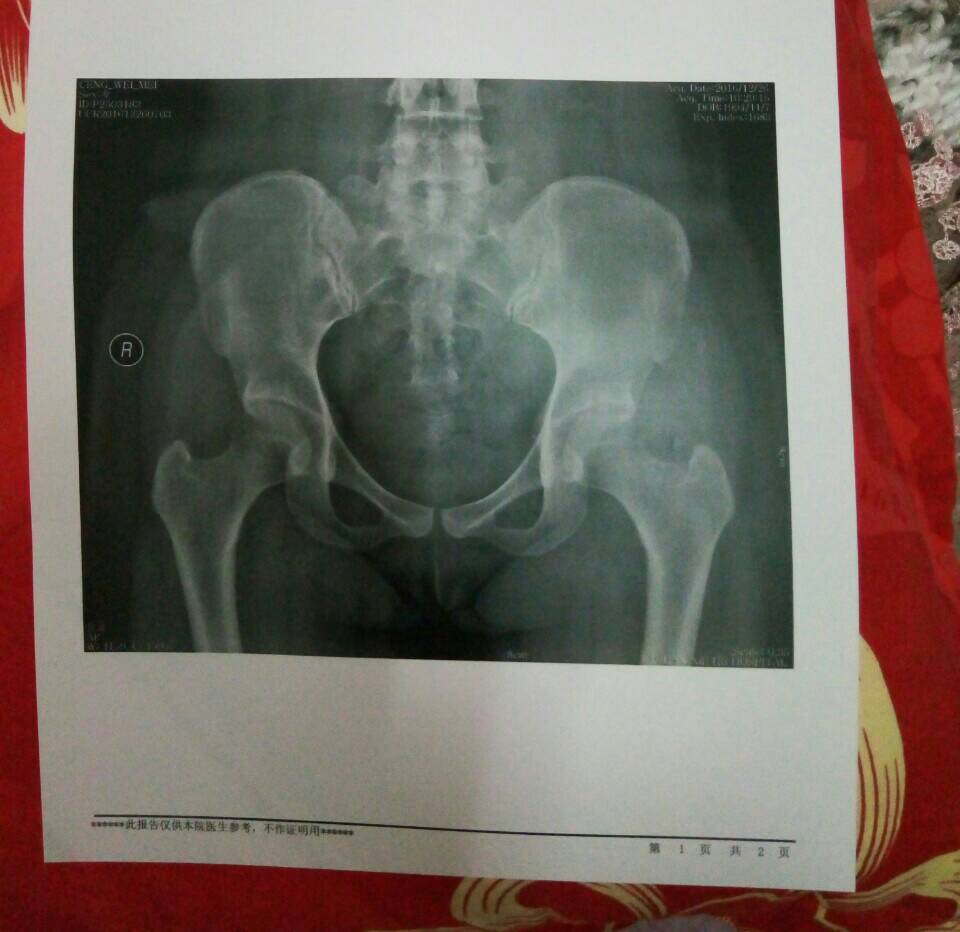

出现股骨头骨质疏松就是股骨坏死,这是刚开始。注意不要负重行走,每天及时补充足量的钙和维生素D,最好能够每天睡前泡脚半小时

我的片子看也是有塌陷,想去做置换,医生看了片子,看我能动作不是很受限,就让我延后再置换

你的很好,现在治可以治好的,要好好看,别跟我的似的弄塌陷了

骨密度不均匀,最好能核磁共振再看看,核磁更准确些